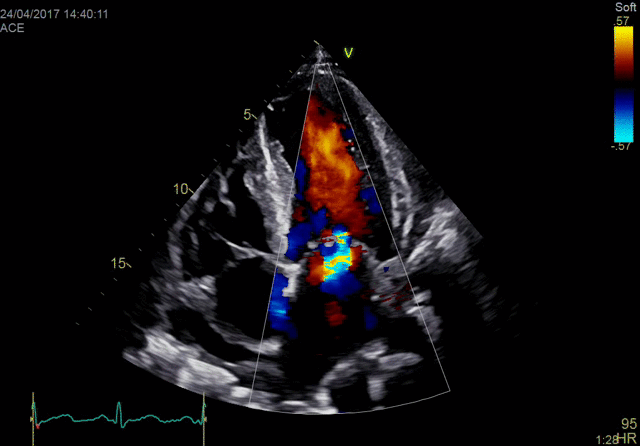

Объединяя проверенную мощность и производительность линейки Vivid с мощной программной платформой формирования ультразвукового луча cSound для реконструкции изображений, система Vivid E90 переносит ультразвуковую диагностику на совершенно новый уровень, помогая минимизировать неинформативные исследования и снизить стоимость услуг.

В сравнении с многими традиционными аппаратами УЗД эта система позволяет получать больше данных, используя технологии точной конфокальной визуализации (TCI) и адаптивного контрастного усиления (ACE) для получения изображений высочайшего качества. Кроме этого система оснащена многими высокоточными инструментами количественного анализа и функциями, оптимизирующими рабочий процесс.

- Детализированное отображение структур сердца для улучшения взаимодействия между врачами УЗД и интервенционными кардиологами (хирургами).

- Улучшенные характеристики:

- качества изображений в ближней зоне обзора;

- четкости отображения латеральных стенок;

- однородности изображений;

- проникновения.